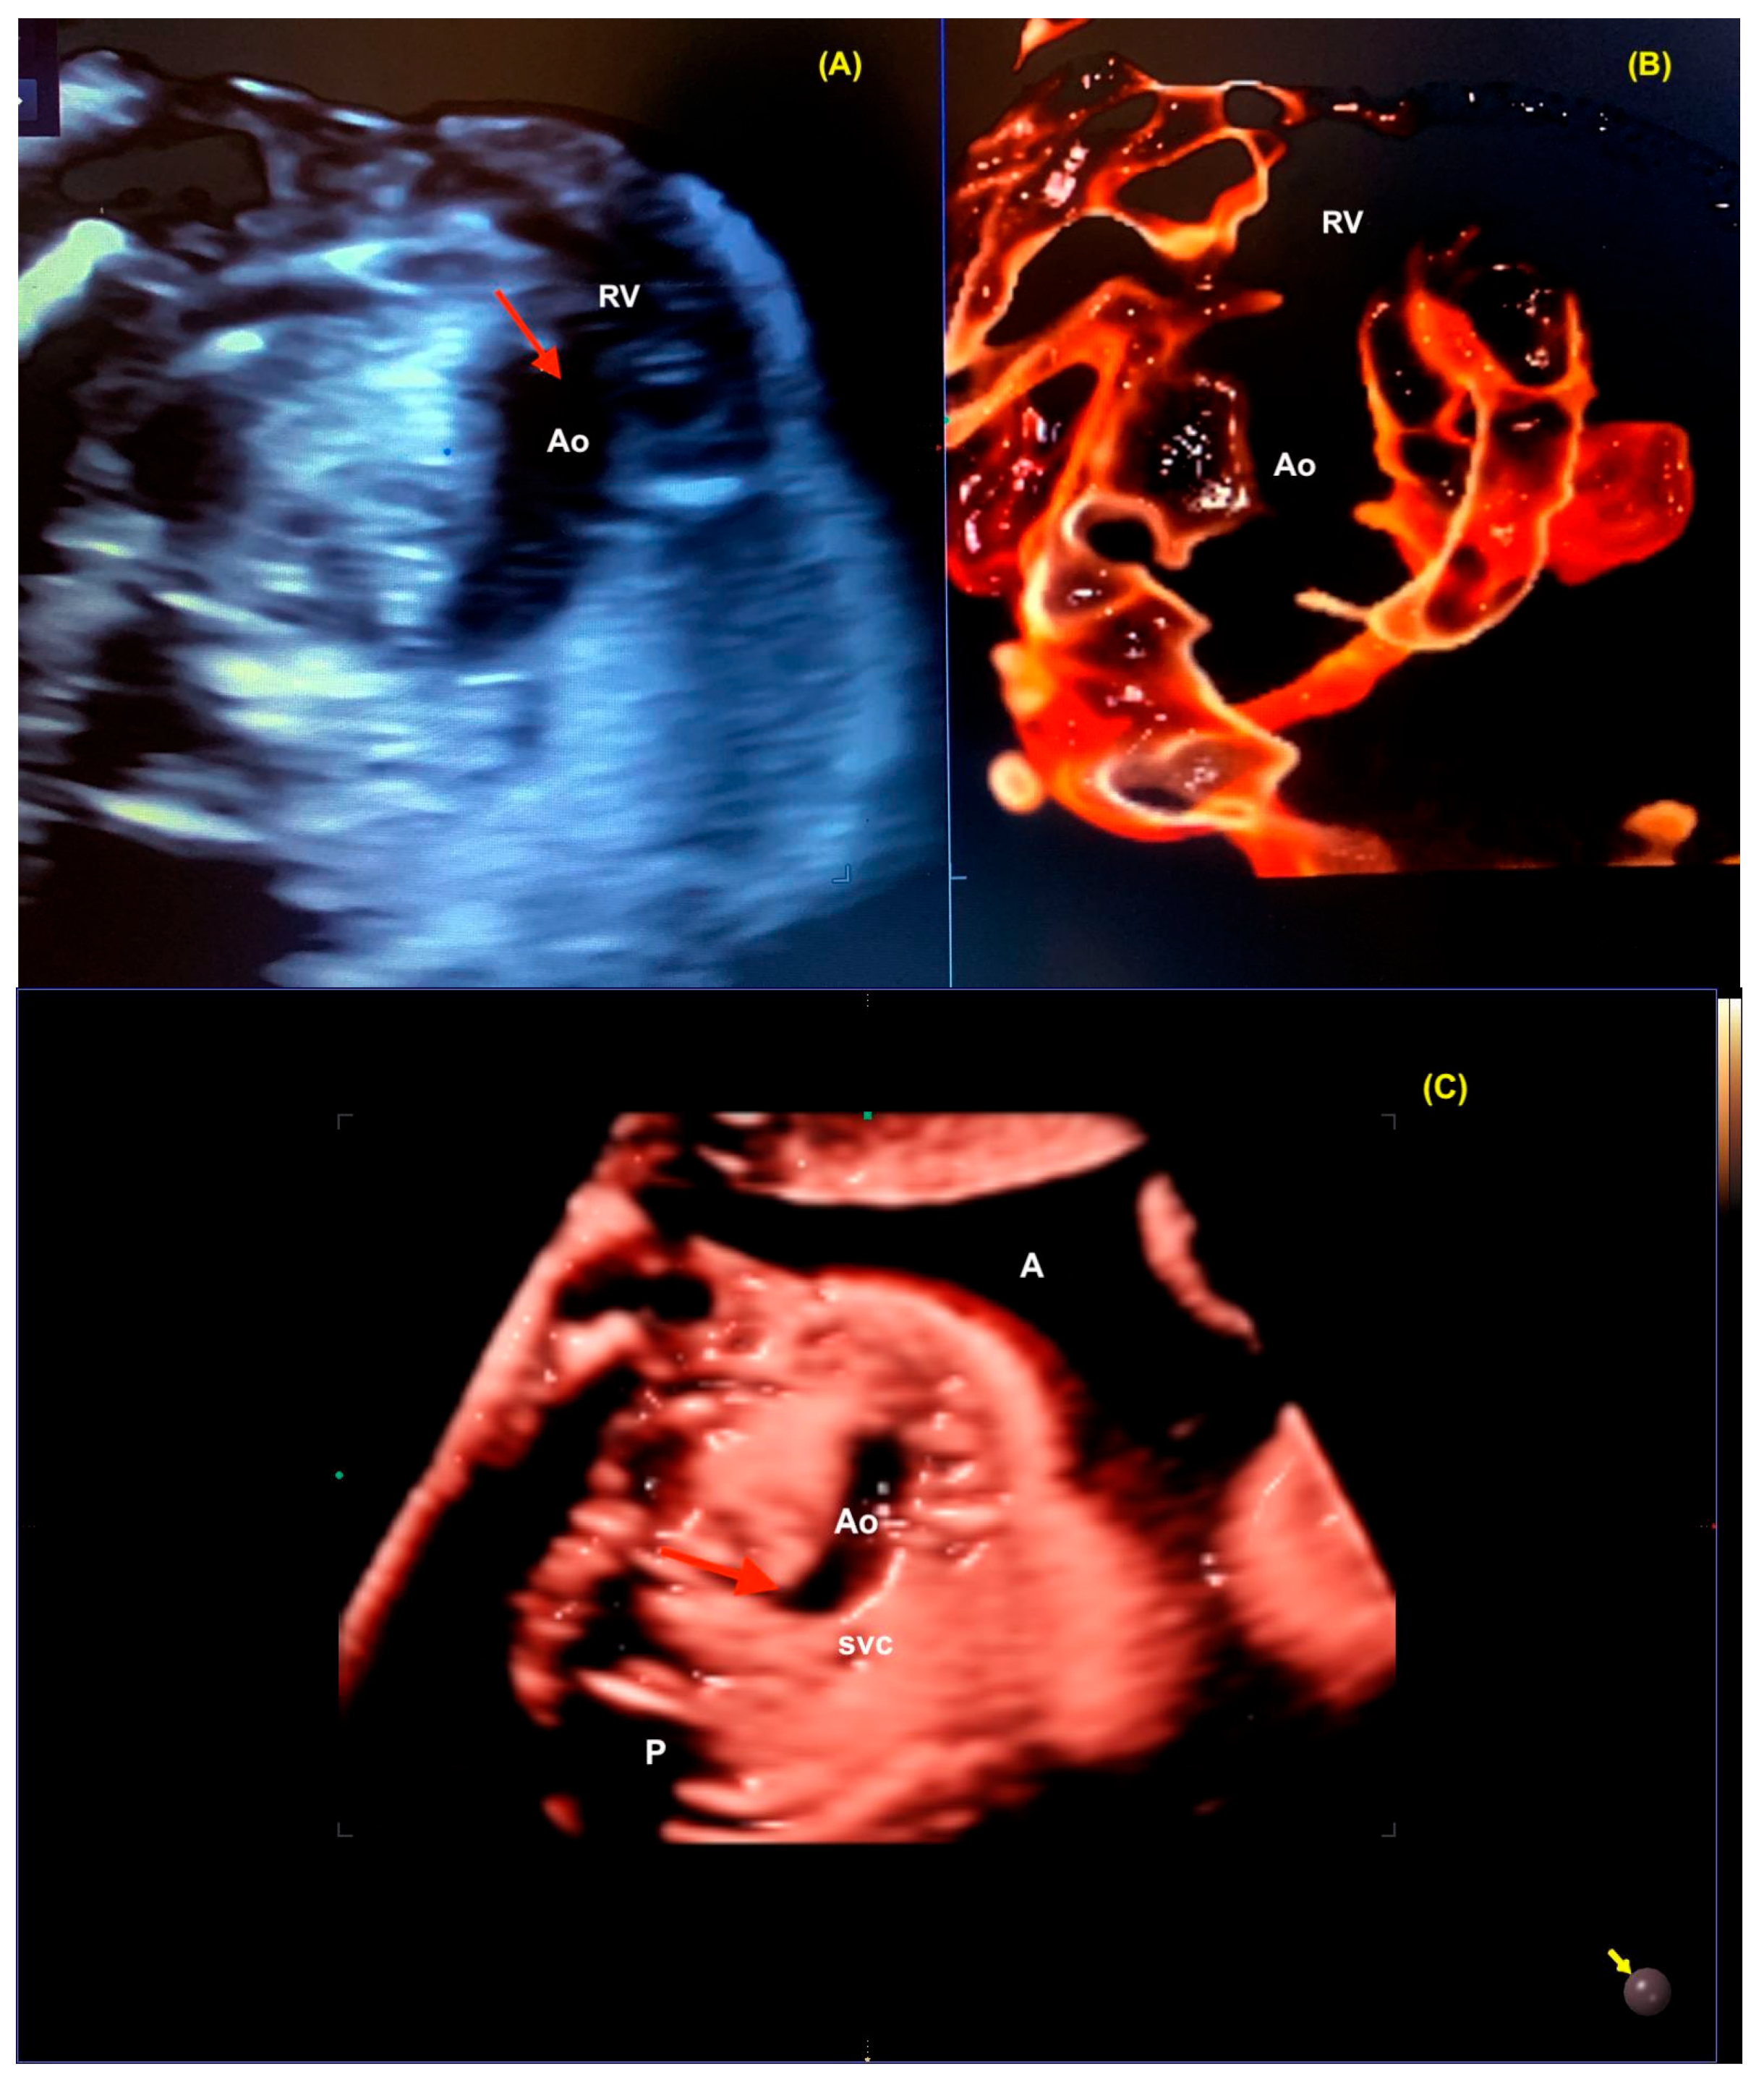

10. Transposition of the Great Arteries

- Shih, J.C.; Shyu, M.K.; Su, Y.N.; Chiang, Y.C.; Lin, C.H.; Lee, C.N. ‘Big-eyed frog’ sign on spatiotemporal image correlation (STIC) in the antenatal diagnosis of transposition of the great arteries. Ultrasound Obstet. Gynecol. 2008, 32, 762–768. [Google Scholar] [CrossRef] [PubMed]